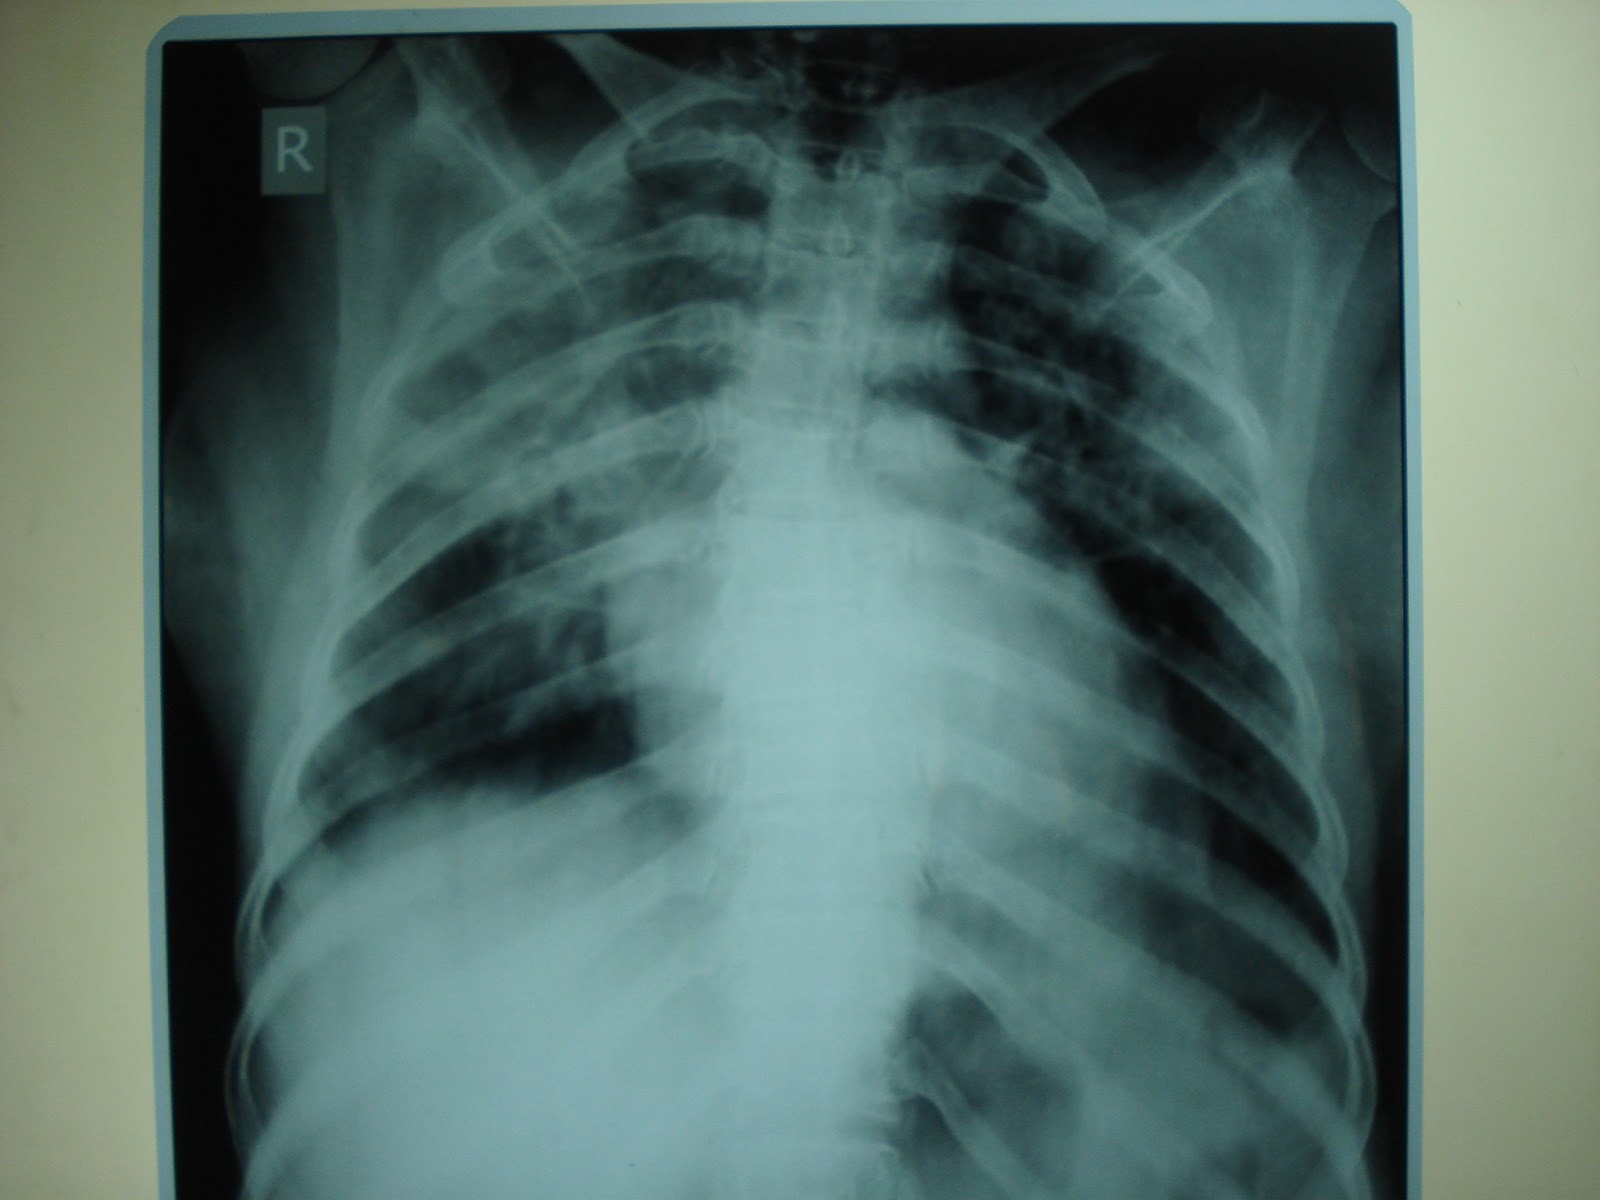

Chest x ray showing streaky pattern due to fluid overload YouTube What Does Fluid Overload Look Like fluid overload means that there is too much fluid in the body. Although the body does need plenty of fluid to remain. It's when you have too much fluid in your body. It can be caused by. hypervolemia, or fluid overload, happens when there is too much fluid in your body. Fluid overload occurs when the body cannot. What Does Fluid Overload Look Like.

Chest X Ray Fluid What Does Fluid Overload Look Like fluid overload means that there is too much fluid in the body. Fluid overload occurs when the body cannot get rid of excess fluid. hypervolemia, or fluid overload, is having too much fluid in the body. Noticeable swelling (edema) in your arms, legs and face. It can be caused by. The body needs just the right amount of. What Does Fluid Overload Look Like.